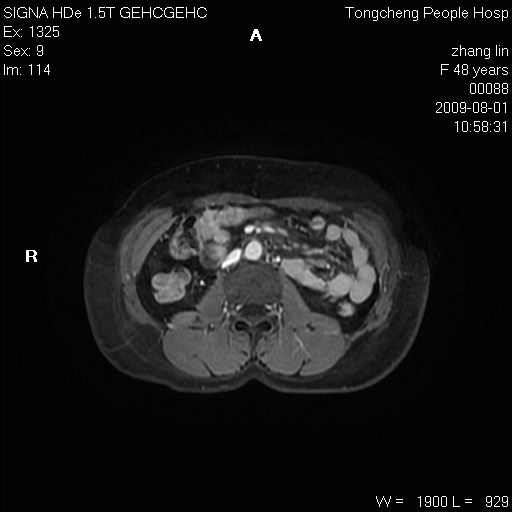

女,48岁。健康体检,彩超发现右肾占位性病变。平素健康。

临床诊断:右肾占位性病变,性质待定(囊肿?肿瘤?)。

上中腹部mr平扫+增强扫描,图像如下:

右肾上极见一类圆形病灶,t1wi呈等信号t2wi呈等高混杂信号,三期增强无强化,边界清---考虑囊肿出血。